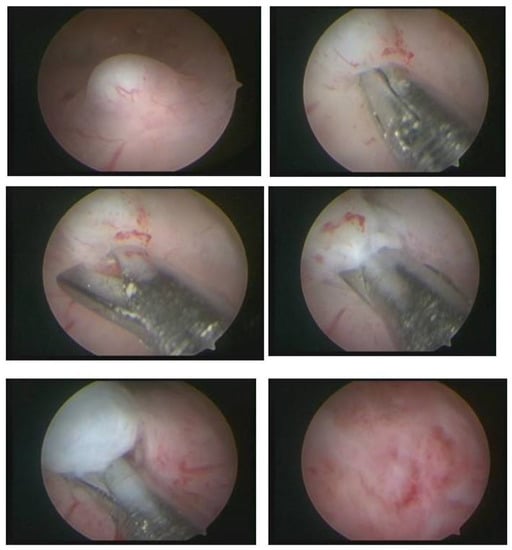

In our service, the most performed technique is using the 5 Fr tweezers or scissors. Initially, the endometrium is incised around the nodule until accessing the plane of the pseudocapsule; then, with the forceps or the body of the hysteroscope, entering between the nodule and the myometrium, the release is initially performed, laterally first and then centrally, until its complete release (Figure 7).

Figure 7. Office hystreroscopic myomectomy with scissor.